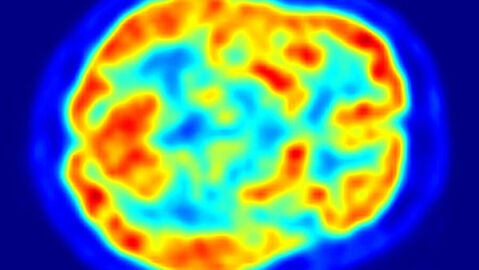

Pero en el caso de la medicina molecular, el armamento indicado son las máquinas PET que, a diferencia de los TAC -Tomografías Axiales Computerizadas- son Tomografías por emisión de positrones. Funcionan por tanto detectando en una zona del cuerpo un haz de positrones, elementos de idéntica masa y carga que el electrón, pero de signo contrario, que la máquina visualiza con gamas de colores para mostrar nuestra actividad metabólica.

La explicación médica del funcionamiento de la FDG es que las células que empiezan a reproducirse de forma anómala al formarse el tumor, como todas las células, se alimentan de azúcar, por lo tanto habrá un mayor consumo de azúcar donde haya más células y esté la probable localización del tumor. La FDG lo que hace es enviar una 'baliza' a las máquinas tipo PET que permite ver no sólo dónde está, sino lo rápido que es el consumo de esa glucosa marcada radiactivamente y, por tanto, lo virulento que es el tumor.